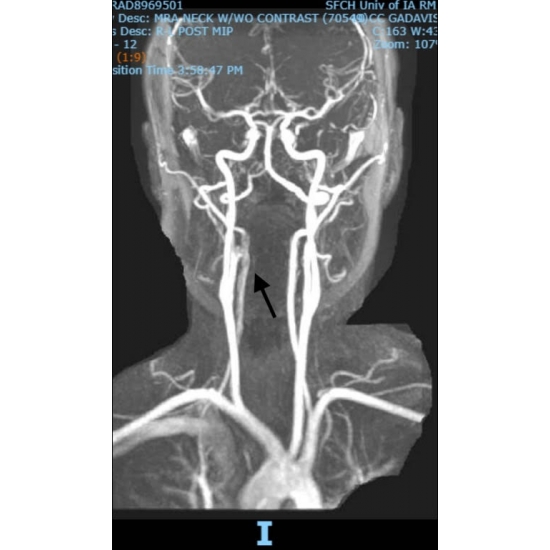

| Do Not Jump To Conclusions - Neck Pain After A High Ropes Course Mishap - Page #3 | |||